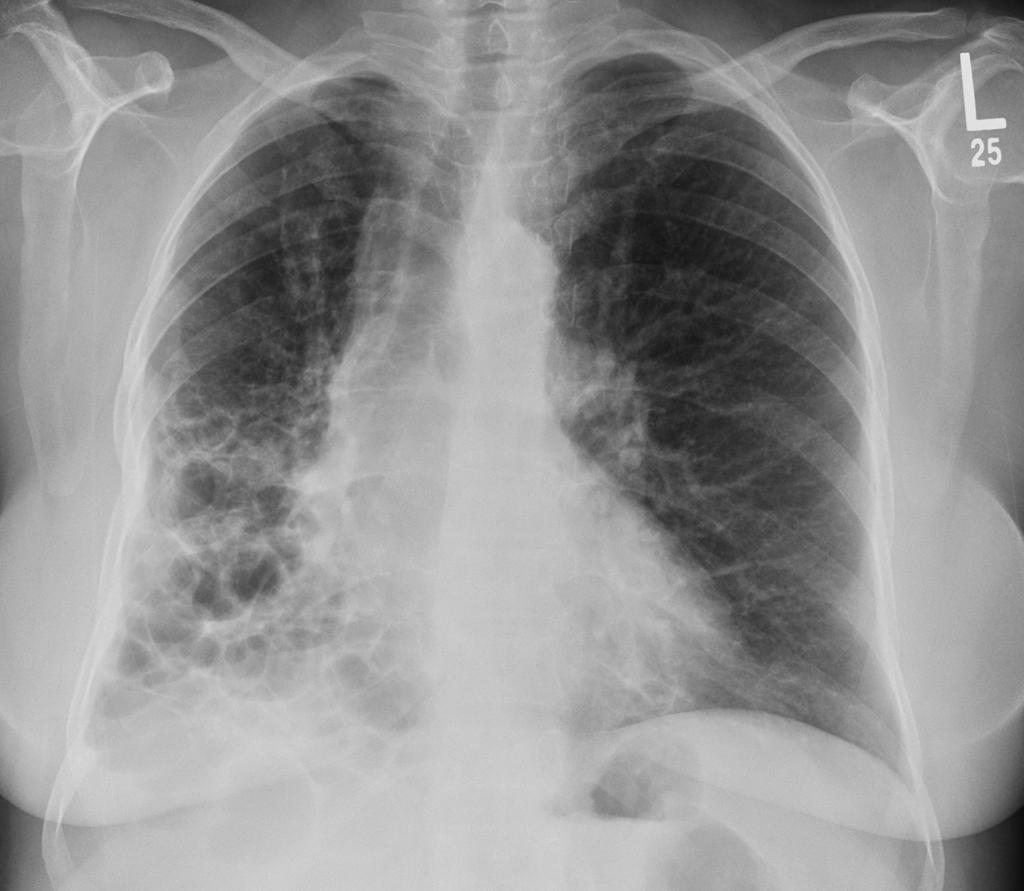

间质性肺疾病的诊断方法与标准

你是不是也有过这样的经历:咳嗽了好几个月,各种止咳药都试过了,但就是不见好转?或者爬个楼梯就气喘吁吁,家人都说你是缺乏锻炼,但你心里总觉得哪里不对劲? 如果这...

间质性肺疾病的临床表现与症状

你有没有这样的经历:明明以前爬三层楼都不带喘的,现在走几步路就气喘吁吁?或者总是莫名其妙地干咳,吃了止咳药也不管用? 如果这些症状持续出现,你可能需要警惕一种...